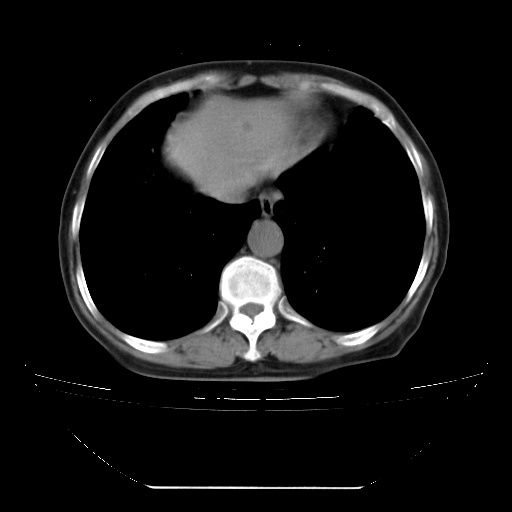

查原发灶吧,肺内转移瘤!肝内也有病灶,需强化明确。

两肺内病灶呈小结节状和树芽状,纵膈的肿大的淋巴结密度不均匀,并见有钙化,多形态病灶,考虑为两肺结核,肝内考虑小囊肿。

以下是引用zhw974247在2009-3-6 6:25:00的发言:[br]两肺内病灶呈小结节状和树芽状,纵膈的肿大的淋巴结密度不均匀,并见有钙化,多形态病灶,考虑为两肺结核,肝内考虑小囊肿。